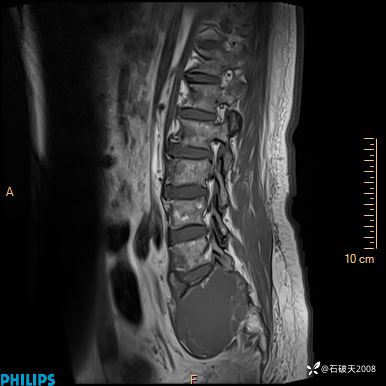

2023年3月份MRI影像

T2矢状位